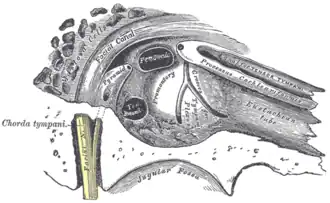

External and middle ear. Eustachian tube labelled as auditory tube. | |

Frontal section through left ear; upper half of section

Frontal section through left ear; upper half of section -